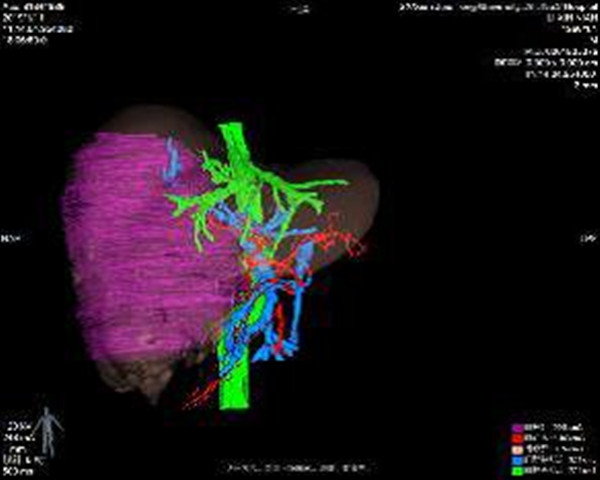

借助普外科3D辅助成像系统术前进行精准评估,实际肝体积3631ml,标准肝体积1288ml,肿瘤体积2048ml,左半肝体积(含尾状叶左半部分)1478ml,除右半肝剩余肝脏体积比标准肝体积大,说明患者左半肝已明显代偿,手术切除是可行的。术前肝功能Child-Pugh A级,ICG 15min滞留率 10.5%,无手术禁忌。

2019年1月26日在科主任陈熹教授、党支部书记吉鸿教授协调下,解放军总医院肝胆外科专家的协助指导下,在王宁麻醉医师、曲文梅器械护士、王丹巡回护士密切配合下,陆宏伟教授团队顺利完成解剖性右半肝切除术。虽然经过术前细致的评估,但是术中实际情况比预想的更加困难,患者肿瘤巨大,周围组织紧密包裹瘤体,并发出大量血管滋养肿瘤,操作空间狭小,每一步操作困难重重。一旦肿瘤再次破裂,大量出血,后果不堪设想。果断地采用前入路切肝方法,先控制入肝血流,再离断并分离右半肝,精细操作,精准解剖,细心结扎每一根血管和管道,完成解剖性右半肝切除术。顺利切除右半肝及尾状叶右半部分。术中及术后患者生命体征平稳,术后无胆瘘并发症,现已恢复正常饮食。为患者进一步治疗,争取了宝贵的时间和机会。